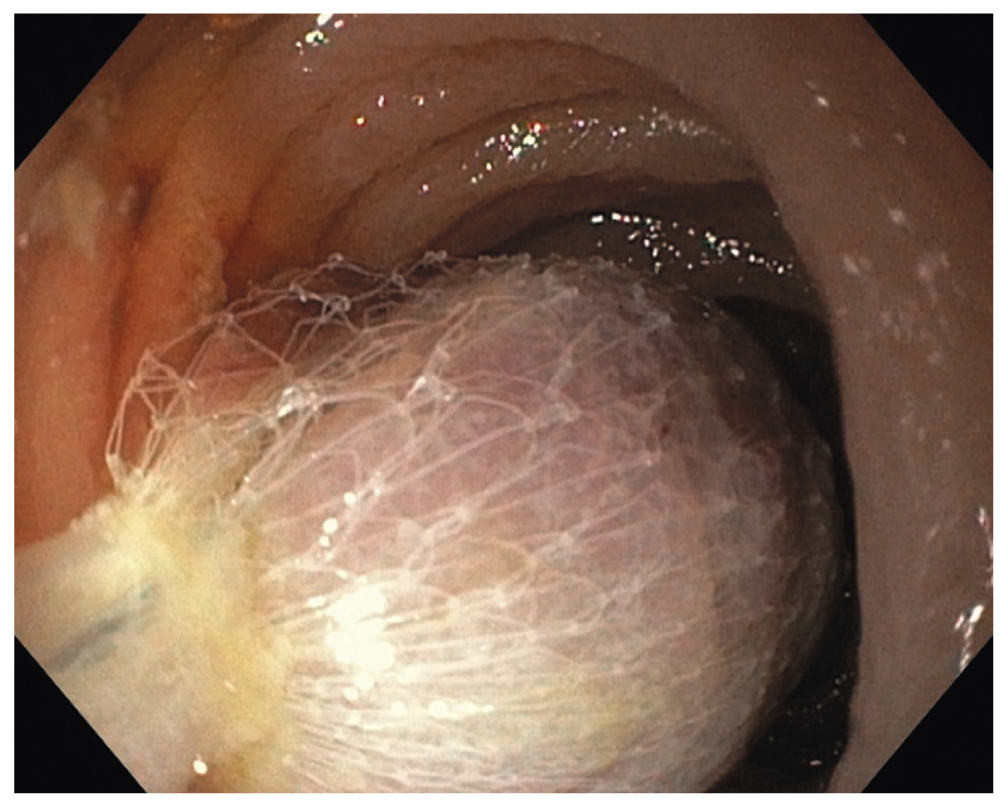

Поскольку в день операции у ребёнка был отмечен очередной эпизод мелены, для исключения поражений Дьелафуа, а также для осмотра тощей кишки на уровне расправленного тонкокишечного инвагината (30–40 см от связки Трейтца) интраоперационным консилиумом принято решение выполнить третье эндоскопическое исследование верхних отделов ЖКТ. В положении ребёнка на левом боку под СО2-инсуффляцией с применением ручного пособия тонкий видеогастроскоп заведён в тощую кишку, где на расстоянии около 40 см от пилорического канала было обнаружено эпителиальное новообразование шаровидной формы размерами 15×17 мм на короткой широкой ножке толщиной около 6 мм (тип 0-Ip по Парижской классификации эпителиальных новообразований) (рис. 6). Поверхность полипа гиперемирована, покрыта единичными округлыми эрозиями с налётом фибрина. Новообразование легко смещалось в просвете кишки при помощи инструментальной пальпации. С целью расширения возможностей инструментария тонкий видеогастроскоп заменён на аппарат стандартного диаметра с рабочим каналом 2,8 мм, который с техническими трудностями, обусловленными малым диаметром просвета ЖКТ у ребёнка, был проведён к новообразованию. Первым этапом с помощью эндоскопического инъектора выполнено введение в подслизистый слой физиологического раствора с индигокарминовым красителем в основание полипа с целью создания гидравлической подушки между слизистой и мышечной оболочками стенки кишки (рис. 7). Отмечен умеренный лифтинг новообразования. Эндоскопической серповидной петлёй Olympus Snare Master 25 мм выполнен захват полиповидного образования в пределах неизменённых тканей и затягивание петли на ножке образования (рис. 8). Выполнено удаление полипа в пределах неизменённых тканей в смешанном режиме коагуляции-резания (электрохирургический блок Olympus) методикой эндоскопической резекции слизистой оболочки. При осмотре после резекции признаков резидуальных тканей новообразования и глубокого повреждения стенки кишки не определялось. Отмечено подтекание крови из ложа удалённого образования. Выполнен гемостаз и сведение краёв дефекта слизистой при помощи трех эндоскопических клипс (рис. 9). Полип извлечён при помощи эндоскопического сачка из просвета ЖКТ и направлен на морфологическое исследование (рис. 10, 11).

Рис. 8. Эпителиальное новообразование захвачено эндоскопической петлёй

Fig. 8. An epithelial lesion is taken by an endoscopic snare

Рис. 9. Пострезекционный дефект слизистой оболочки укрыт тремя эндоскопическими клипсами

Fig. 9. The post resection defect of mucosa is closed by three endoscopic clips